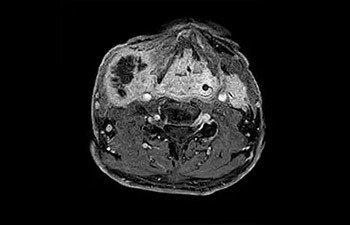

• Baanbrekende versnellingstechniek waarmee niet alleen sequenties versneld worden, maar uw gehele MRI-onderzoek. • Unieke implementatie waarmee 2D- en 3D-scans tot wel 50% sneller gemaakt kunnen worden met een nagenoeg gelijkwaardige beeldkwaliteit.1

• Kan gebruikt worden in alle anatomische contrasten en alle anatomieën.

met Compressed SENSE